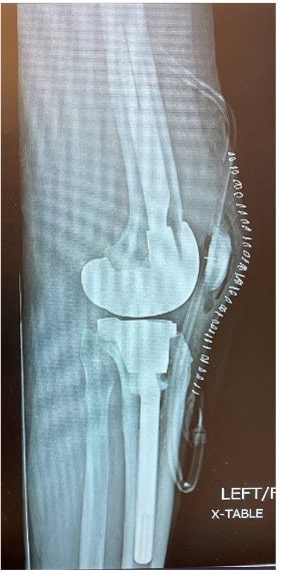

The 74-year-old patient with left TKA implanted two years ago (Figure 1) complained of persistent anterior knee pain, limited range of motion, and dissatisfaction. Given the patient’s severe dissatisfaction with his knee replacement, a revision knee arthroplasty was indicated for component malrotation and arthrofibrosis.

The patient tested negative for infection with a well healed midline incision, his active range of motion was 10 degrees to 85 degrees, and he was stable to varus and valgus stress throughout his range of motion. On radio graphs, he had a cemented posterior stabilized implant with no peri-implant lucency, migration, or subsidence which appeared to be slightly flexed. On the sunrise view he had a patella showing an increased lateral tilt. A pre-operative CT scan was obtained to evaluate for component position and rotation given the limited knee flexion and concern or malrotation. The tibial component was measured to be 10 degrees internally rotated with respect to the tibial tubercle.

At the 6-week postoperative clinical exam, the x-rays showed good positioning of implants (Figures 5 and 6). The patient was doing well showing great signs of pain relief with increased stability and function.